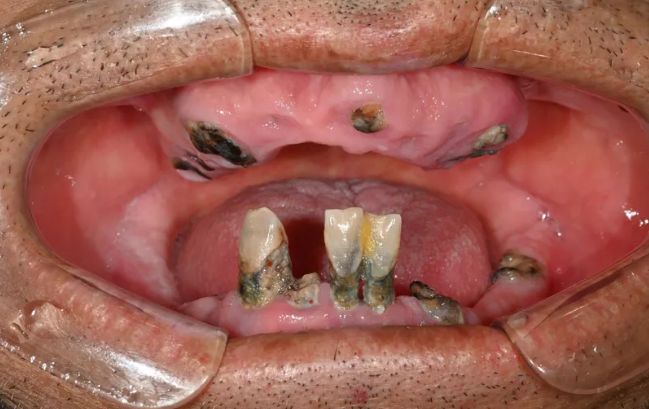

2022-03-0560대 남성, 수면 전체 임플란트 13개 식립

-

2021-09-06